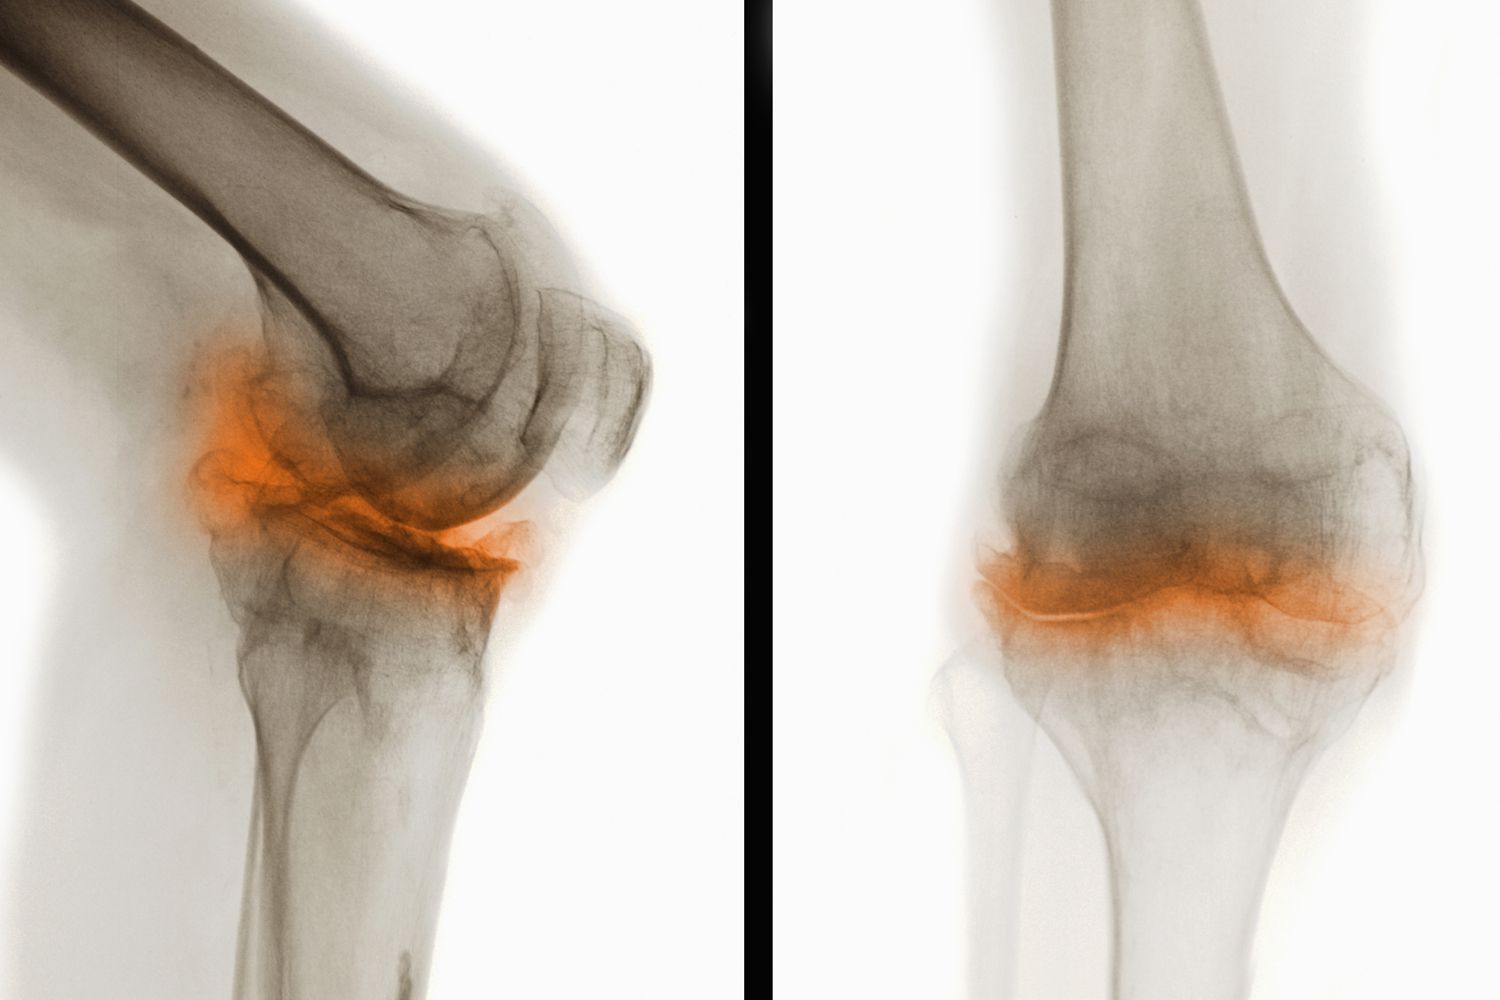

骨關節炎(Osteoarthritis,簡稱OA)是一種常見的慢性退行性關節疾病,主要表現為關節軟骨的退化和破壞,導致關節疼痛、僵硬和功能障礙。這種疾病通常發生在中老年人群中,尤其是負重較大的膝關節、髖關節、脊柱及遠側指間關節等部位。